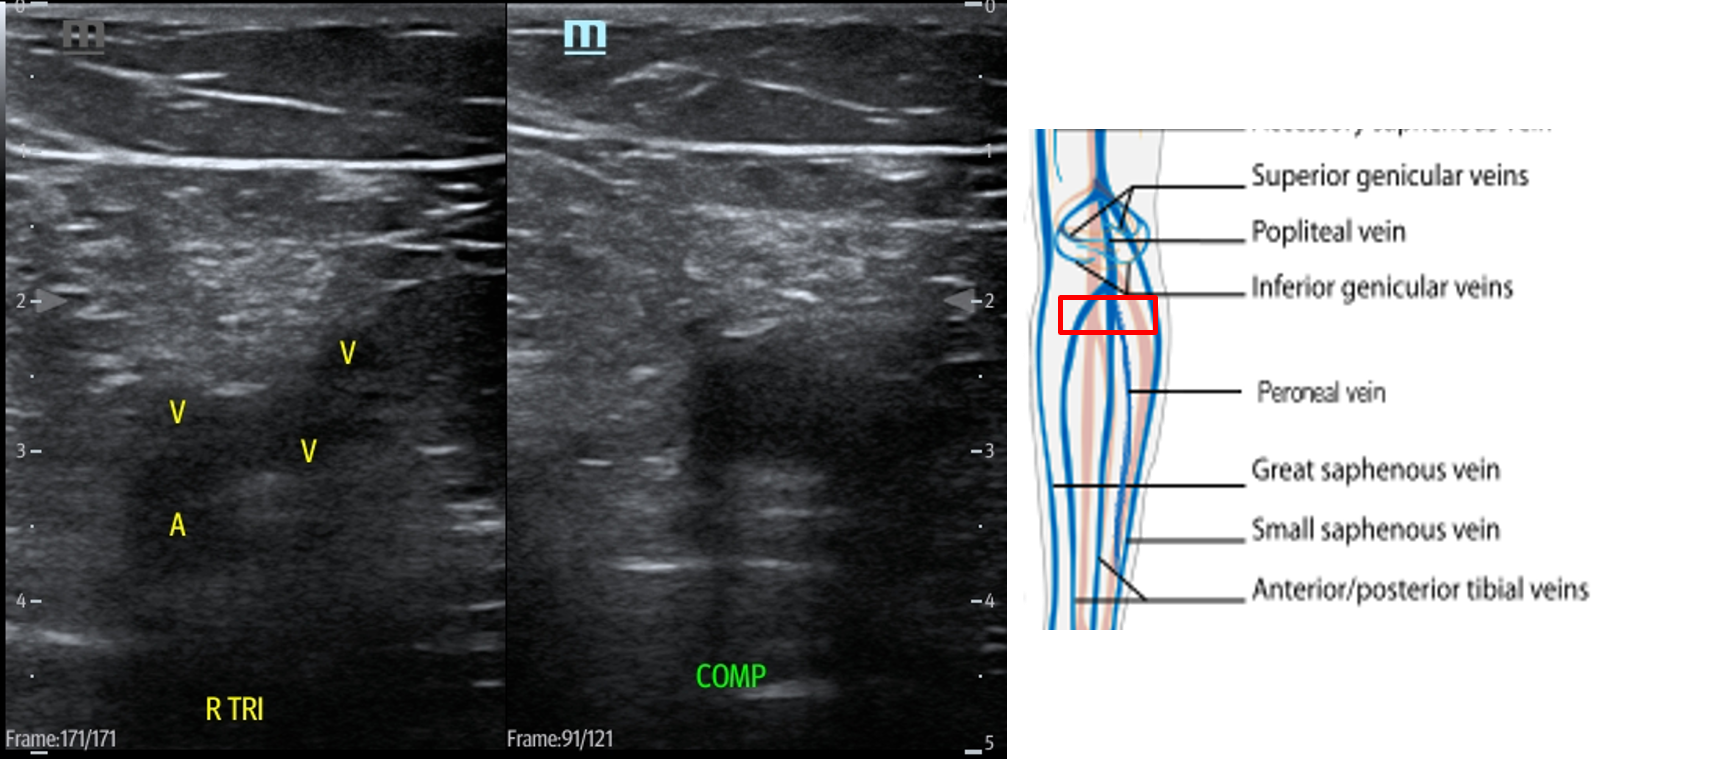

- Slide the transducer distally until you see the PV trifurcate into the PTV, ATV and peroneal vein. (Fig. 15) Compress each of these veins. This constitutes completion of evaluation of “region 2.”

- Figure 15. Compression of the PTV, ATV and peroneal vein in the distal portion of the popliteal fossa just before they converge into the popliteal vein with transducer orientation indicated (red rectangle).

- In a retrospective study of 808 lower limb venograms, 42% of studies were noted to have two veins visualized in the popliteal fossa, and 31% of studies involved duplicated superficial femoral veins.4